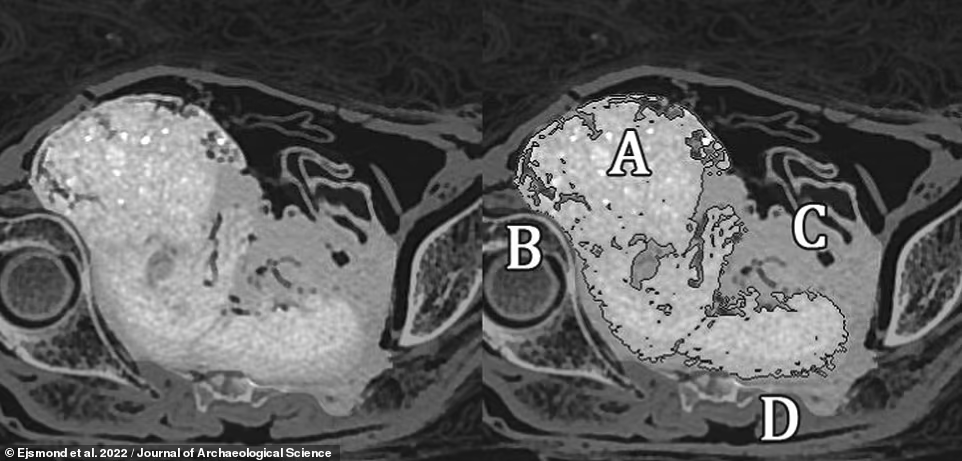

扫描发现了木乃伊腹中的胎儿。

研究小组解释说,在木乃伊中,从胎儿骨骼中浸出的矿物质会沉积到胎儿的组织和周围的子宫中,使两者具有更高的辐射密度,从而在CT扫描中呈现出不同的外观。